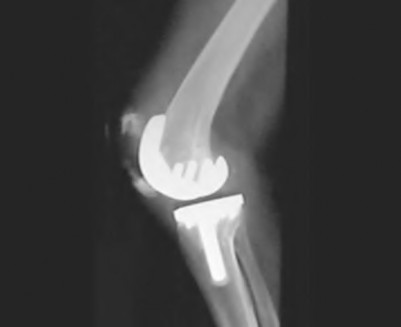

During a revision total knee arthroplasty, removal of the tibial component reveals a massive contained metaphyseal defect measuring 3 cm deep, but with an intact cortical rim. According to the Anderson Orthopaedic Research Institute (AORI) classification, what type of defect is this, and what is the preferred method of management?